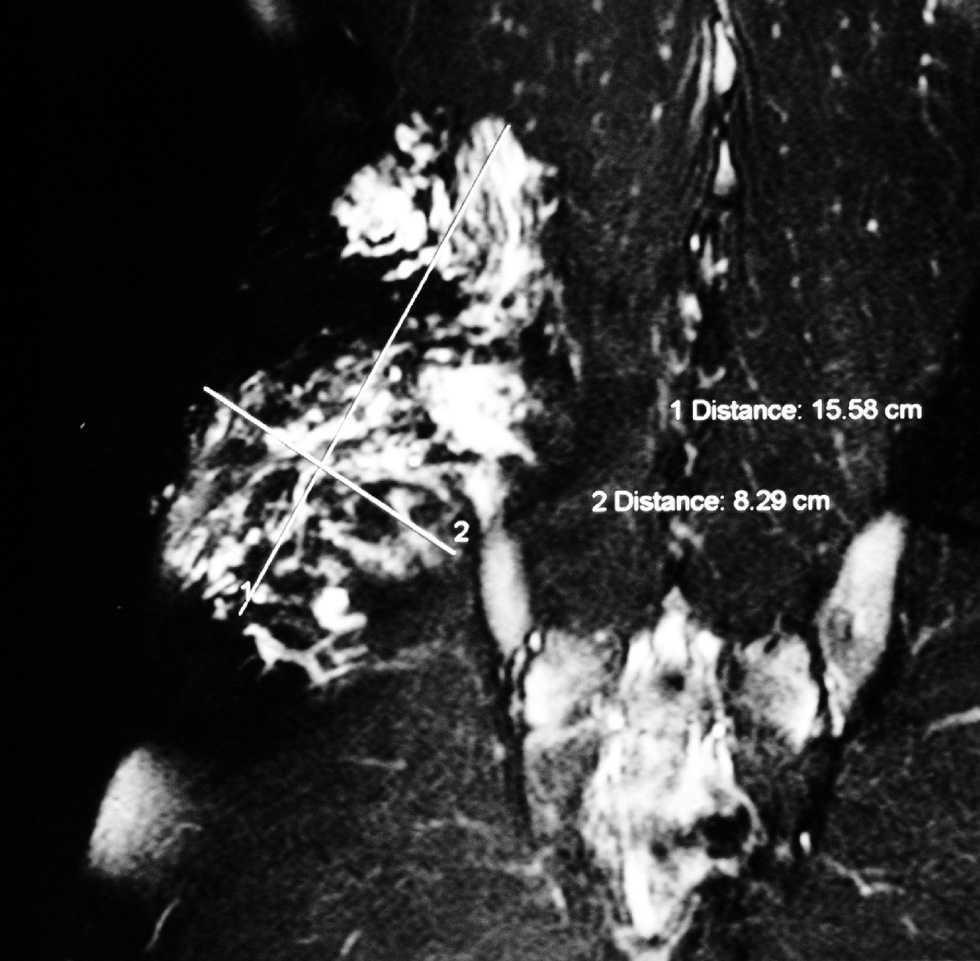

Con el objetivo de valorar la extensión en profundidad se solicitó estudio de resonancia magnética (RM) de región lumbar derecha y pelvis, donde se visualizó una masa retroperitoneal de contornos mal definidos e irregulares, que envolvía el músculo ilíaco derecho y desviaba anteriormente el músculo psoas homolateral (fig. 2). Dado el componente profundo extenso y el antecedente de recidiva, desestimamos toda intervención terapéutica, optándose solamente por el seguimiento periódico de la lesión y el control de posibles complicaciones asociadas.

Fig. 2.--Estudio de resonancia magnética en el que se evidencia una masa retroperitoneal de contornos mal definidos e irregulares, que envuelve el músculo ilíaco derecho y desvía anteriormente el psoas homolateral.